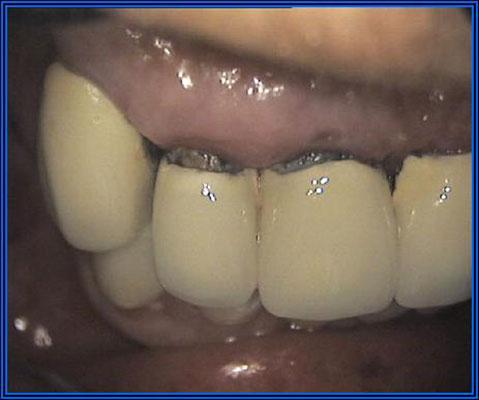

Sette giorni dopo l’inserimento delle viti di guarigione fig.10 si passa all’inserimento dei provvisori che resteranno fissi per circa 2 mesi fig.11-12. Questi provvisori facilitano la programmazione per la realizzazione dei definitivi e guidano la crescita della gengiva fig.13 in modo corretto intorno ai denti per avere un effetto estetico migliore.

Successivamente si preparano i monconi fresati con strutture in lega aurea fig.14-15, si passa alla ceramizzazione delle strutture, quindi rifinitura, lucidatura e inserimento in bocca delle corone ormai pronte e definitive fig.17-18-19.